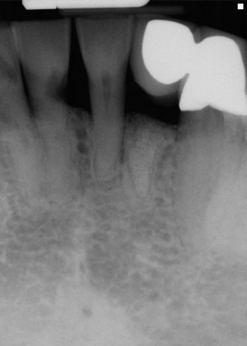

The young man was evaluated at 2 weeks (Figure 25 and Figure 26) and again at 6 weeks (Figure 27). The remaining natural teeth and the implant were stable. The natural teeth had a reduction in mobility to plus 1 at most. The patient's expectation was met. The soft-tissue element of his smile was maintained, and the patient is considering more cosmetic dentistry to optimize his smile. At 16 weeks postoperatively, the radiograph suggested that the digital workflow provided a great benefit to the patient and reduced the amount of chair time in the dental practice, with help from digital technology and the dental laboratory (Figure 28).

Fig 16. Preoperative periapical radiograph on the day of surgery.

Figure 16

Fig 25. Postoperative periapical radiograph at 2 weeks.

Figure 25

Fig 28. Postoperative radiograph at 16 weeks.

Figure 28